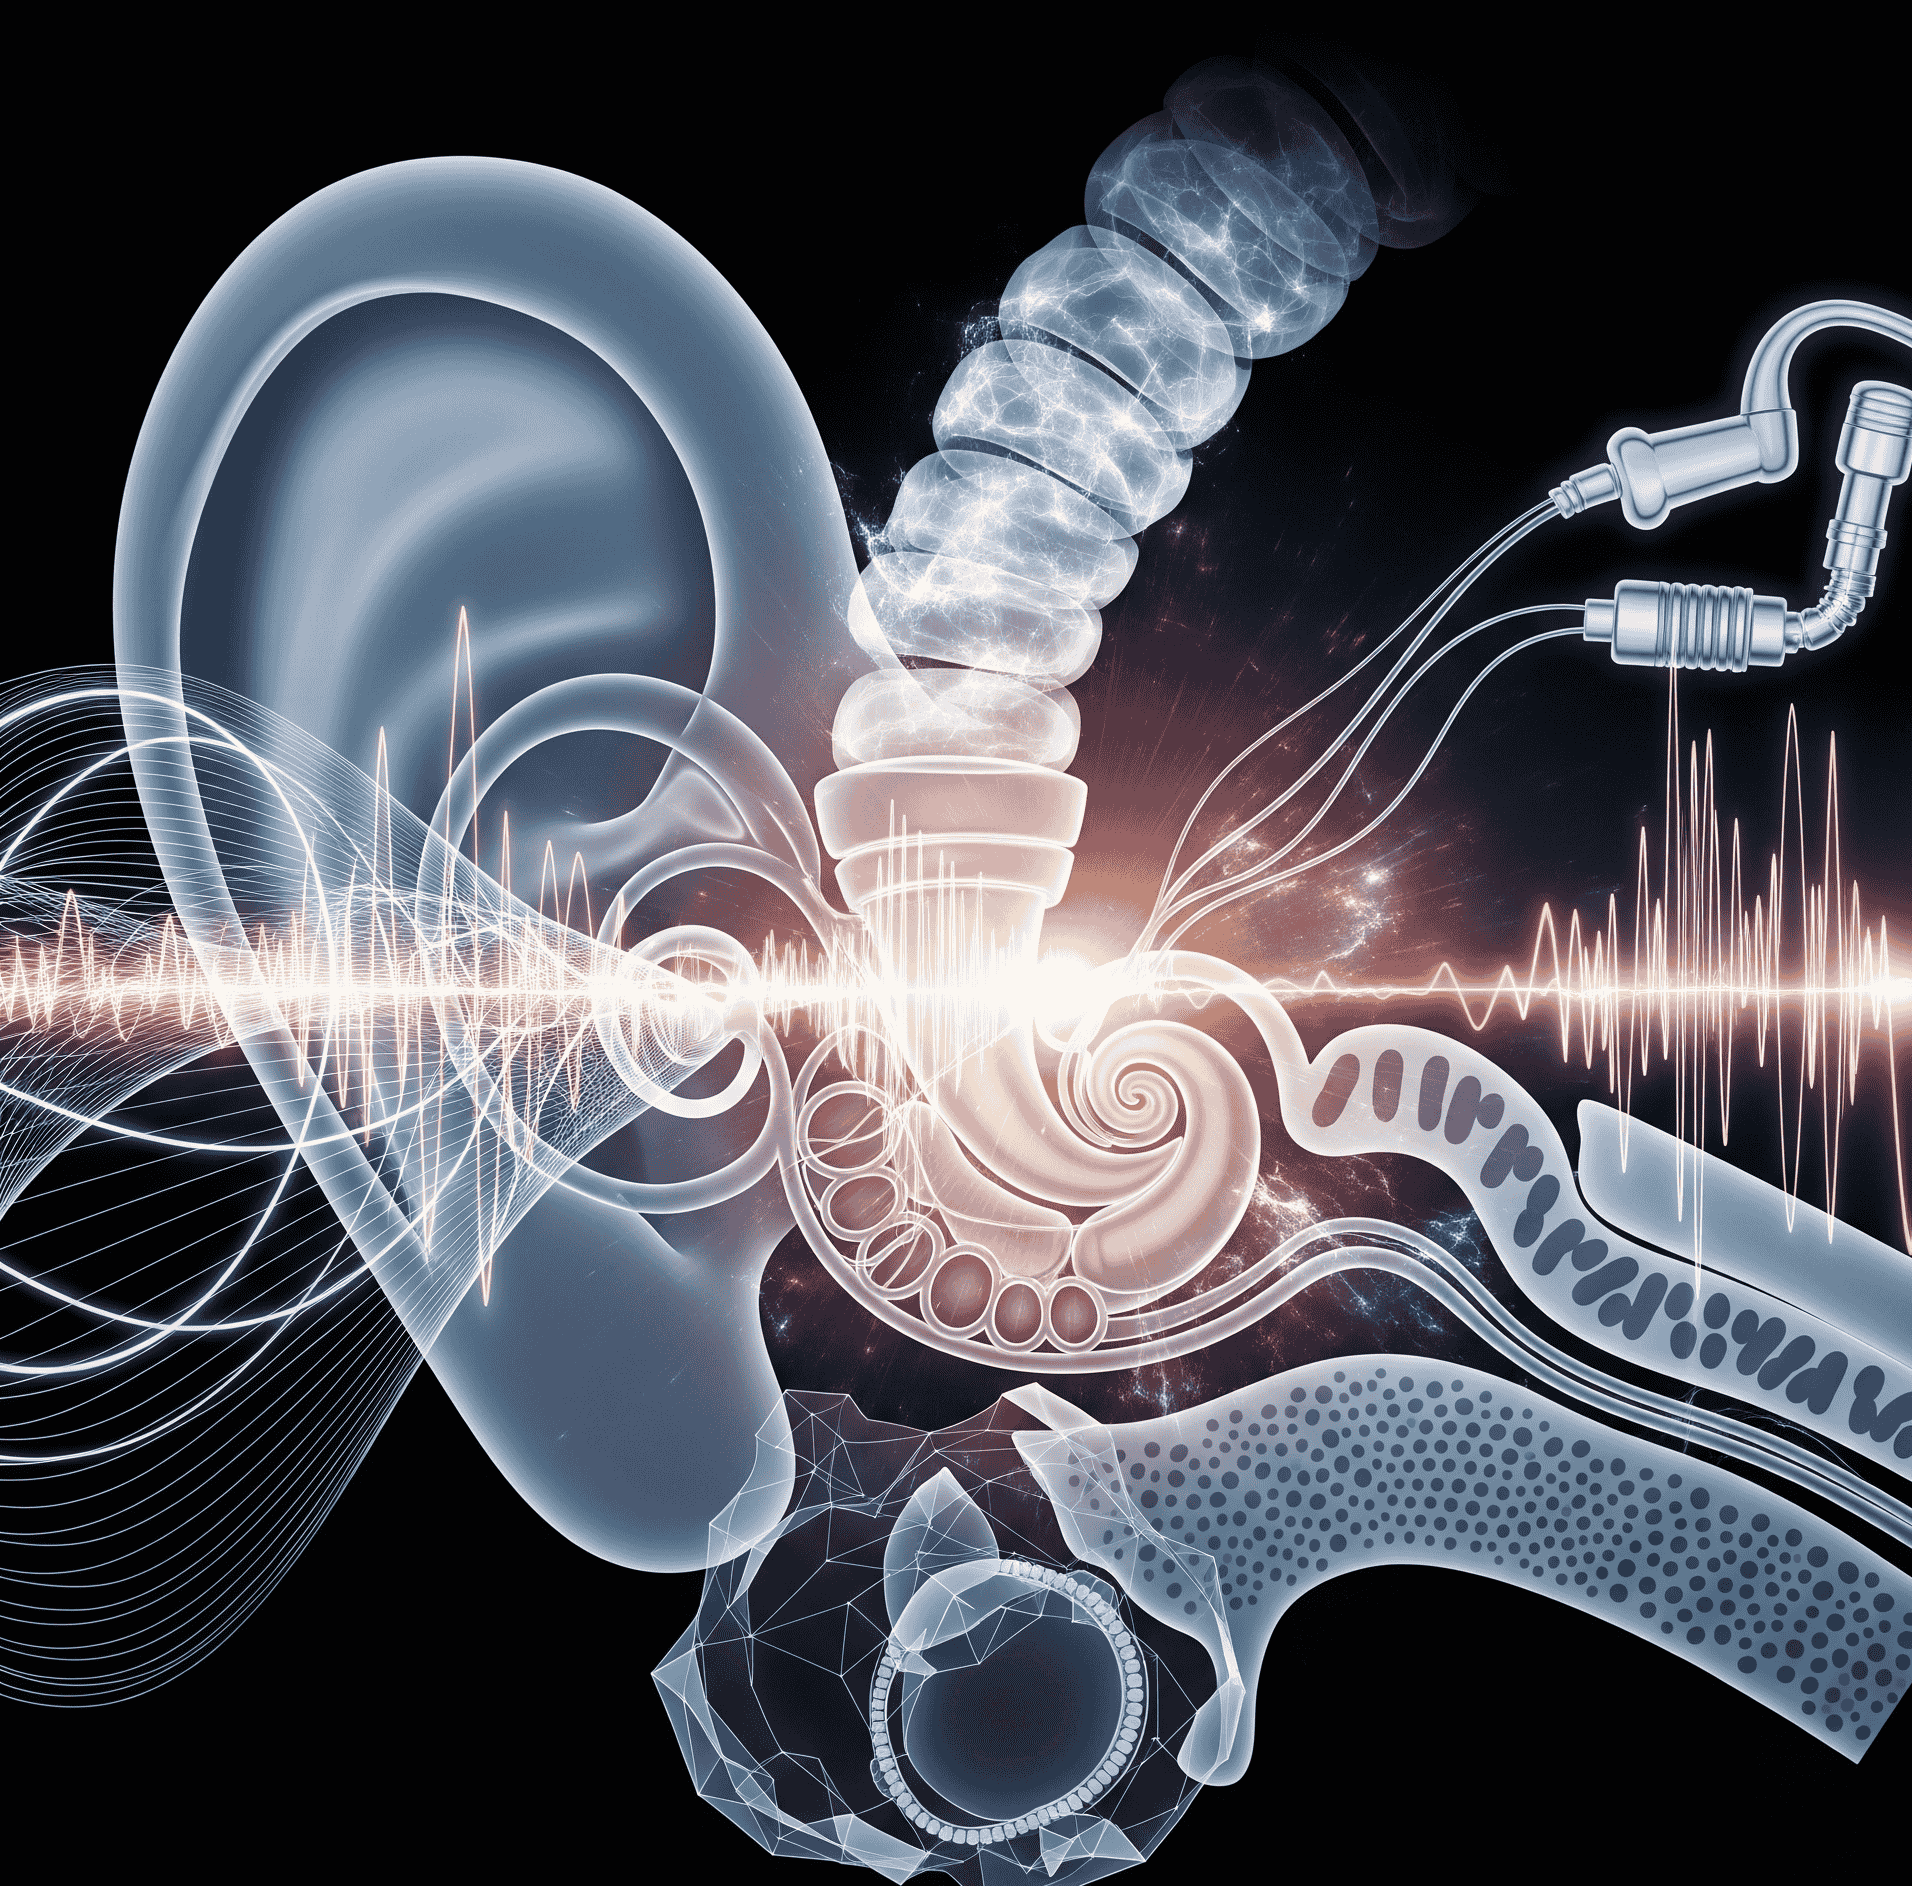

Otolaryngic & Auditory Health Journal

Otolaryngic & Auditory Health Journal, an Emiko MedTech publication, serves as a dynamic, peer-reviewed academic nexus dedicated to the scientific and clinical frontiers of ear, nose, throat, and comprehensive hearing health...